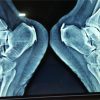

The first case was a 73-year-old male patient. He had been treated for hypopharynx (stage T1N2bM0) and esophageal cancer by radiotherapy five years ago, when he was 68 years old. The total radiation therapy dose was 70 Gy, consisting of 50 Gy of radiation to the hypopharynx and esophagus, followed by a 20 Gy boost. The lesion disappeared after treatment completion, and no recurrence has been observed. He began to experience neck pain five years after the radiotherapy, and a neck collar was prescribed. However, within a few days, his neck pain (visual analog scale; VAS was 9/10) and cervical kyphotic alignment progressed, and he developed unilateral upper extremity paresis [3 according to the Manual Muscle Test (MMT), right arm] and paresthesia. In addition, he complained about swallowing difficulties due to a neck kyphotic change. A blood examination showed a leukocyte count of 4400/mg and a C-reactive protein (CRP) level of 8.30 mg/dL; an elevated inflammatory response was observed. Severe kyphotic deformity and distraction of the C4 vertebrae, and expansion of the retropharyngeal space were shown in radiography (Fig. 1a). Computed tomography (CT) revealed destruction of the C4 vertebrae and erosion of the C5 vertebrae (Fig. 1b).